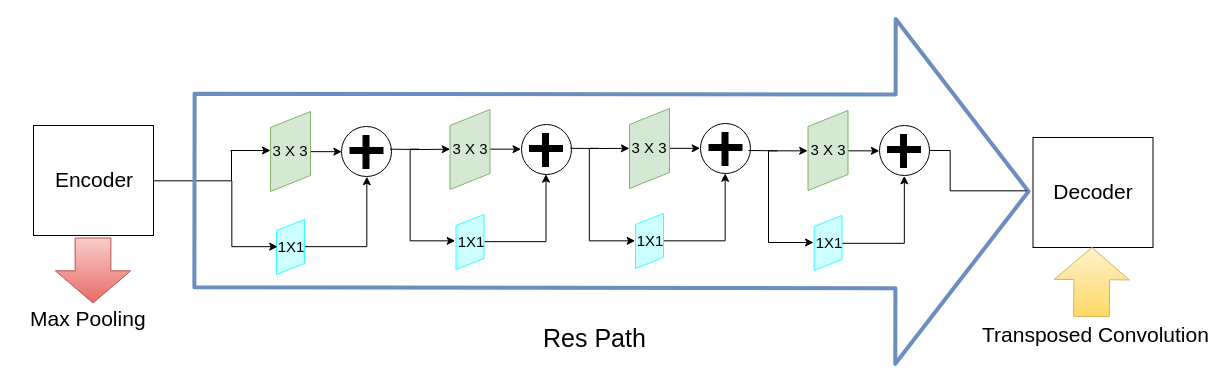

MultiResUNet

The generic design of this network is quite similar to that of U-Net, except for slight differences in the nature of convolutions in each layer and the residual path from the encoders to the decoders (Figure 2). Each layer of U-Net is replaced by a MultiRes block that contains 4 convolutions (Figure 2(b)). The skip connections of U-Net are replaced by Res Paths (Figure 2(c)) as described in [25]. The motivation of adopting this network comes from the idea that an ideal architecture should be able to assess images having diversified scales in medical image segmentation procedures. For further details readers are referred to [25].

(c) Res Path Figure 2: MultiResUNet architecture. Figure borrowed from [25]. -